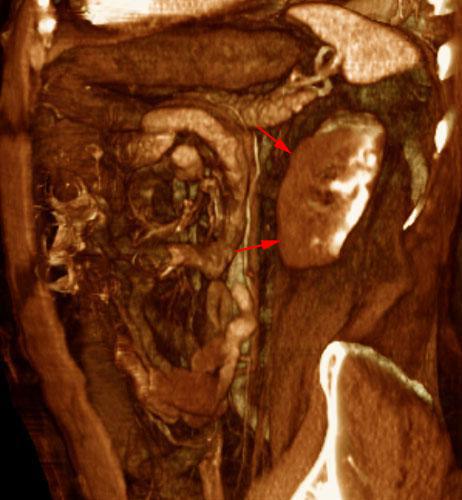

Infarto renal agudo